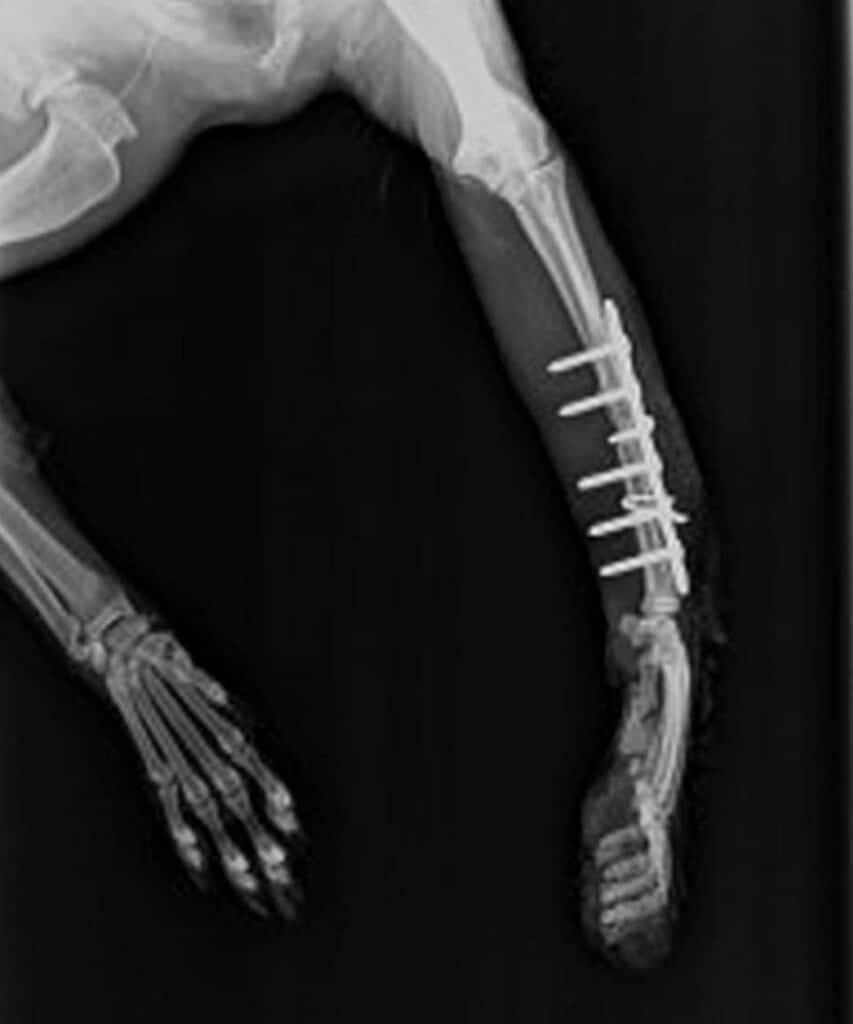

Mit der Knochenschirurgie für Kleintiere haben wir 2026 unser Angebot erweitert.Zur Knochenchirurgie zählt auch die Versorgung einfacher Knochenbrüche bei Hunden, Katzen und anderen kleinen tierischen Freunden.

Mit moderner Ausstattung, viel Erfahrung und ganz viel Herz sorgen wir dafür, dass Ihr Liebling schnell und sicher wieder auf die Pfoten kommt.